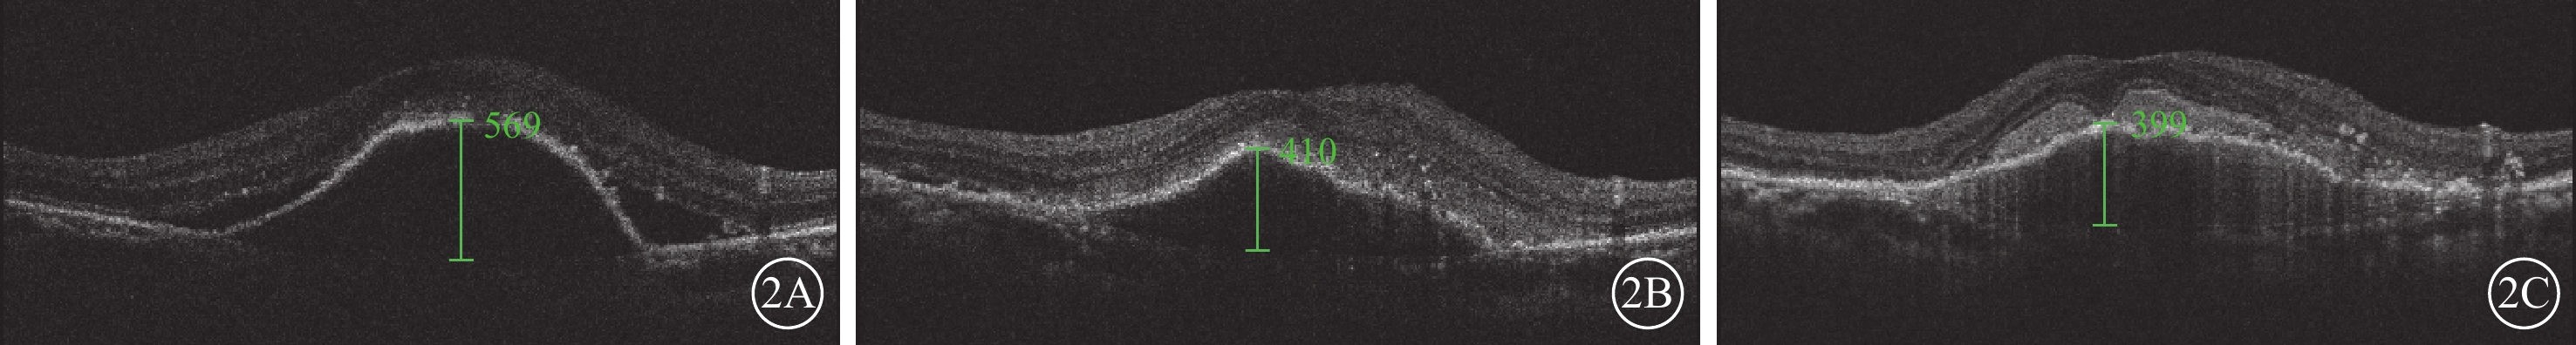

與治療前PEDH比較,治療后3個月,sPED組、fPED組、hPED組患眼PEDH差異均無統計學意義(P>0.05);治療后6、12個月,PEDH差異均有統計學意義(P<0.05),其中hPED組患眼PEDH降低幅度較fPED組、sPED組更大(圖2~4)。與治療前比較,治療后3、6、12個月,3組患眼PEDA、PEDV差異均有統計學意義(P<0.05),其中hPED組PEDA、PEDV較基線改善幅度顯著大于sPED組、fPED組,差異有統計學意義(P<0.05)(表2)。